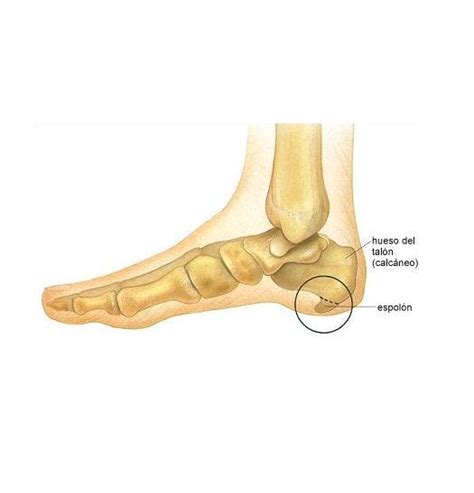

¿Qué es el espolón calcáneo?

¿Qué es el Espolón calcáneo? ¿Por qué aparece y por qué duele?